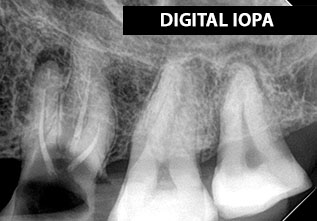

DIGITAL IOPA (INTRAORAL PERIAPICAL)

This dental procedure code, refers to a type of X-ray known as periapical. This term is used because these X-rays capture the entire tooth all the way down to the tissues at the tip of the tooth root – an area referred to as the periapical area.

A periapical X-ray will show one or two teeth in their entirety in one single image, right from the crown of the tooth which is the part exposed in the mouth to the very tips of the tooth roots located in the jawbone, as well as the surrounding bone supporting this tooth.